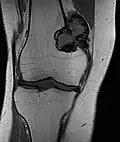

Korrespondierendes Bild der koronaren T1-Sequenz -

Riesenzelltumoren finden sich in etwa 3/4 der Fälle an den Extremitäten und in einem Viertel der Fälle am Rumpf. An den Extremitäten sind Riesenzelltumoren weitgehend auf die Epiphyse der langen Röhrenknochen beschränkt und dort neben dem Chondroblastom der häufigste gutartige Knochentumor. Durch die Lage in der Epiphyse sind sie somit fast immer gelenknah. Die häufigste Lokalisation ist in der Hälfte aller Extremitäten-Riesenzelltumoren das Kniegelenk mit der distalen Femurepiphyse in 34 % und der proximalen Tibiaepiphyse in 29 %.[3] Riesenzelltumore können, auch wenn deutlich seltener, im Bereich der Wirbelsäule auftreten.[4]